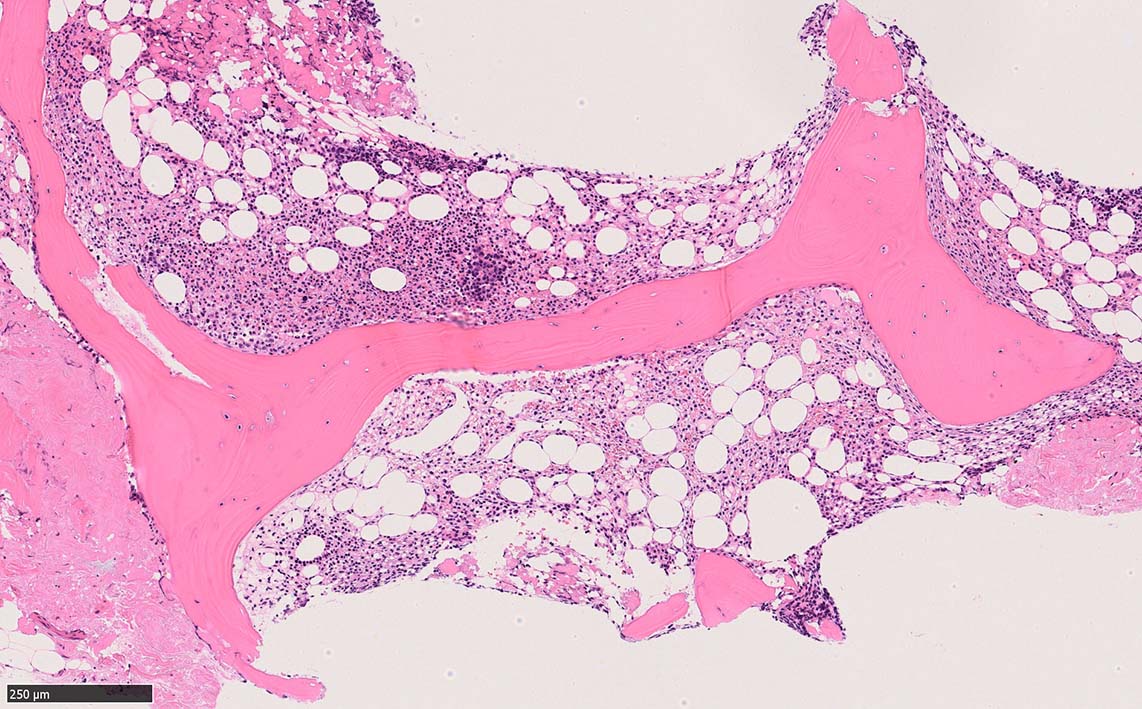

骨髄生検

bone marrow trephine biopsy: dry tapのため骨髄生検が行われる. cellularityは40-80%とhypercellular marrow. 流れのある細胞配列は線維化を疑わせる.

ASD-G 低倍率所見では赤芽球血島は幼若赤芽球の集簇巣が散在する, 顆粒球系細胞(ASDに赤く染色される)は減少,granulopoietic hypoplasiaを呈する.疎な集簇を示すmast cellsの増加がある.

ASD-G陰性の細胞がびまん性に増加しているように見える.

ASD-Giemsa陰性の細胞がシート状に増殖する. 核はクロマチン濃染, 核小体は不明瞭.類円形, 卵円形, くびれを持つ多稜形核, 長円形いびつで屈曲した核, など多彩. 細胞質は淡清色調, 広く淡明. 赤芽球血島は幼若赤芽球のみで形成される異形成像を示す. やや離れて成熟赤芽球が疎な集簇を示す.